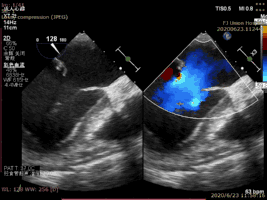

病例2術(shù)前二尖瓣反流為重度